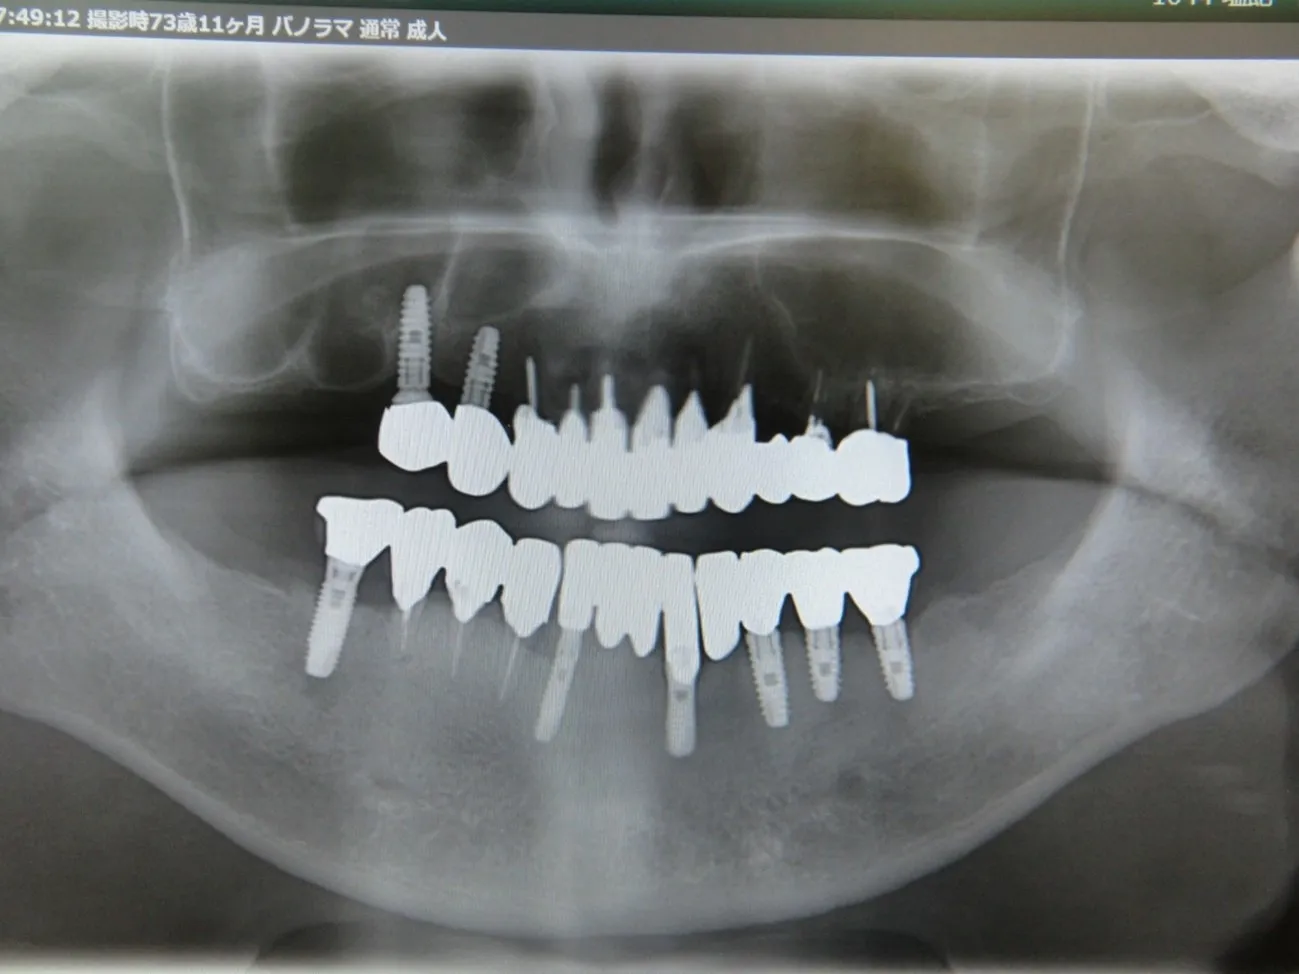

施術を検討されている方に様々なケースの施術前後の違いをご確認いただけるよう、インプラントやインビザラインでの矯正の症例を画像も用いて一覧にして載せております。「ずれている前歯を揃えたい」「受け口を直したい」「抜けた歯をキレイに整えたい」など、様々なご相談を承り、ご予算や仕上がりのご要望はもちろんのこと、長期的な口腔の健康維持も考慮したプランをご提案いたします。